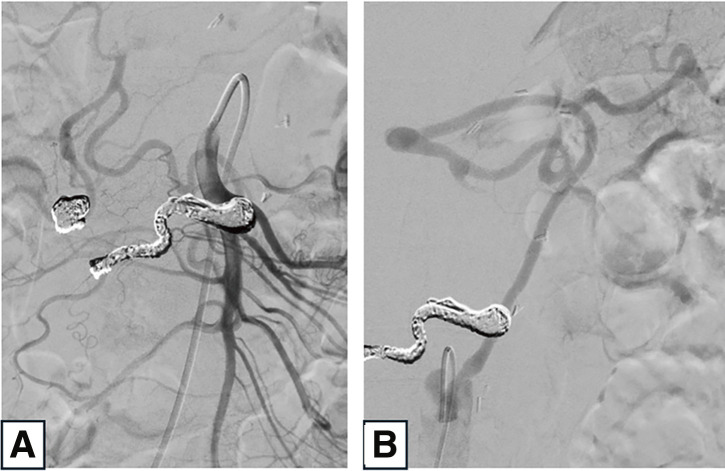

Herein, we describe the case of a 72-year-old man who presented with a residual inferior pancreaticoduodenal artery aneurysm following the rupture and treatment of a superior pancreaticoduodenal artery aneurysm. Open surgery for pancreaticoduodenal artery aneurysms requires carefully planned vascular reconstruction to prevent organ ischemia and minimize pressure changes caused by fluctuations in mechanical stress. Additionally, in cases of rupture, factors such as the patient's condition, presence of hematoma and adhesions, and pressure changes resulting from prior transarterial embolization must be considered. This case report outlines the surgical strategy employed for managing the residual inferior pancreaticoduodenal artery aneurysm.